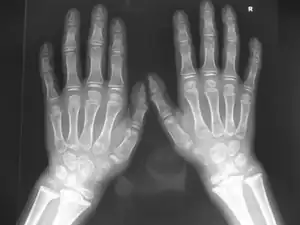

( Marshall-Stickler overlap) Anteroposterior hand radiograph showed, short-stubby hand with large carpal bones associated with pseudoepiphyses of a joint.